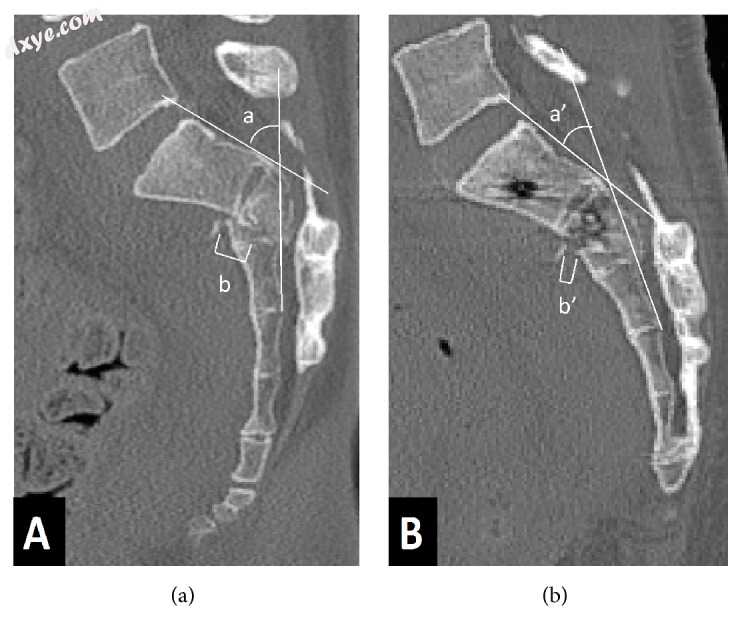

Dennis III区骶骨骨折的骶骨后凸角度是通过测量后骶骨皮质之间的角度来测量的,后骶骨皮质位于横向骨折水平的上方和下方。还通过测量横向骨折上方和下方骶骨前皮质的位移,从矢状位CT重建测量骨折平移(图2)。所有涉及术前,术后和最终X光片的测量以及CT图像均由第一作者进行。

2.jpg

图2

放射学测量方法。 (a)显示了矢状平面中骶骨的术前CT扫描。 (b)显示了矢状平面中骶骨的术后CT扫描。 a和a':骶骨后凸角; b和b':骶骨骨折翻译。